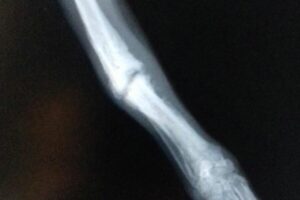

Im Rahmen der Kastration wurde auch Ricardas rechtes Vorderbein geröntgt. Die italienischen Tierärzte möchten nicht mehr daran rühren, aber wir lassen die Röntgenaufnahmen noch in Deutschland von einem Spezialisten für Orthopädie begutachten und hoffen, dass der lieben Hündin doch noch geholfen werden kann!

Ricardas gebrochenes Bein wird am 19.04. durch eine Operation stabilisiert. Damit stehen ihre Chancen sehr gut, dass sie ihr Bein bald wieder vollständig und schmerzfrei belasten kann!